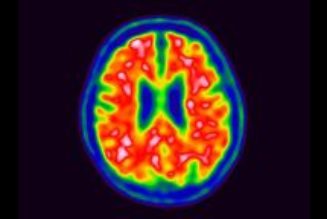

According to Healthline, there are several signs that may indicate that your blood sugar levels are high.

High blood sugar levels can cause the kidneys to try to remove excess glucose from the body, leading to an increase in urination.

2. Increased Thirst: As you urinate more frequently, you may also experience an increase in thirst, as your body loses more fluids.

3. Dry Mouth And Skin